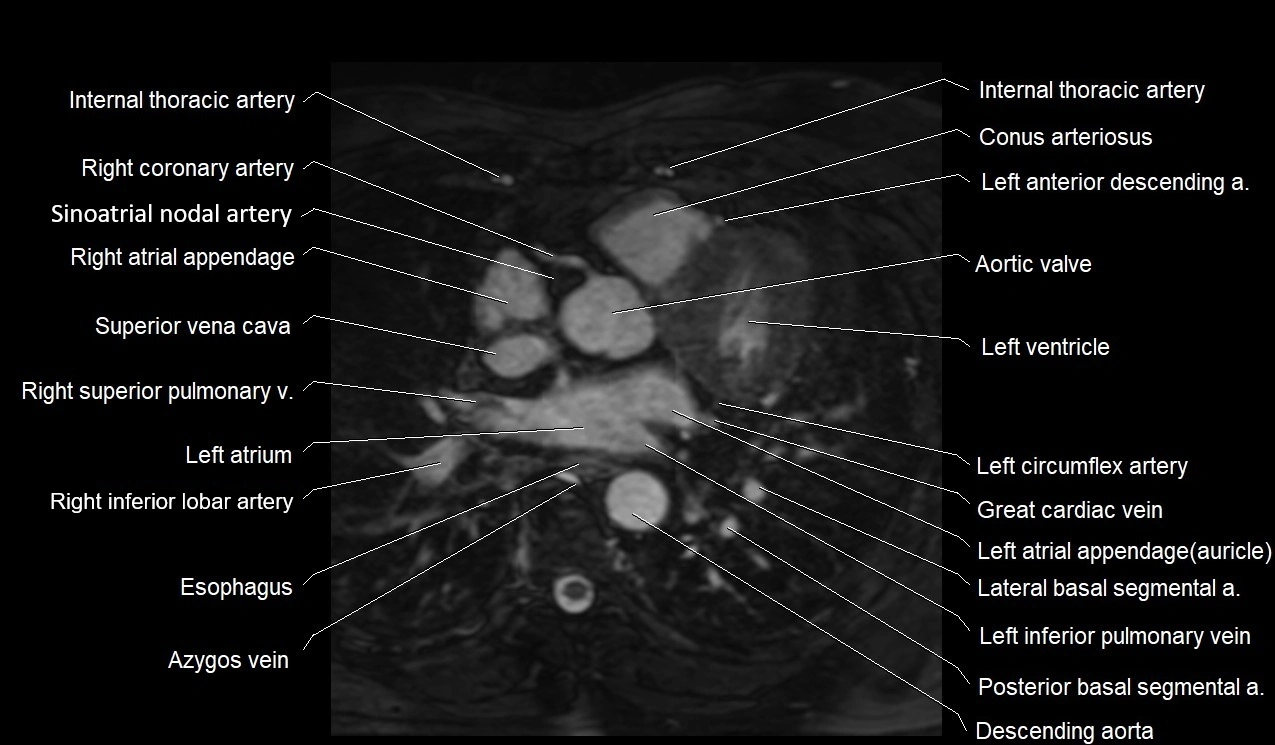

MRI image